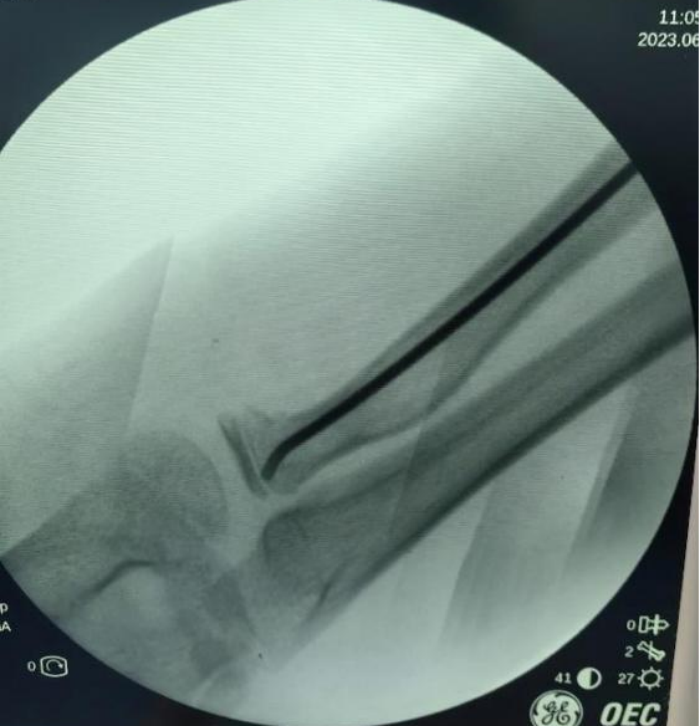

X線顯示:橈骨頸骨折端成角大于30°。骨科主任醫(yī)師錢鈞提醒,這種情況下后期發(fā)育畸形的可能性大,建議手術(shù)治療。

錢鈞組織骨科團(tuán)隊(duì)研討手術(shù)方案,決定為毅毅實(shí)施“橈骨頸骨折閉合復(fù)位彈性髓內(nèi)針內(nèi)固定術(shù)”。

采用該術(shù)不用切開骨折端,創(chuàng)傷小,切口僅為1.5cm,術(shù)后疤痕小,不影響美觀,且手術(shù)時(shí)間短,固定穩(wěn)妥,利于肢體功能恢復(fù)。術(shù)后第2天毅毅即順利出院。